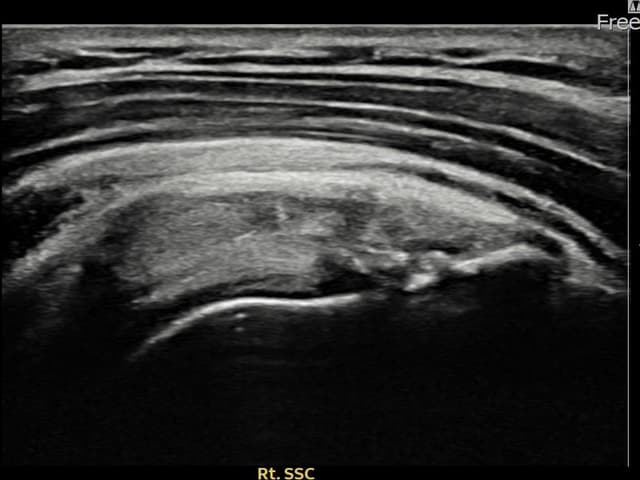

[経過期間: 24.03.04~24.05.10]

[縫縮術] 超音波検査にて右 견갑하근건 関節面側部分断裂(7mm × 3mm (腱厚の約28%欠損))を確認。縫縮術施行後、腱の連続性が回復し、日常生活に復帰されました。